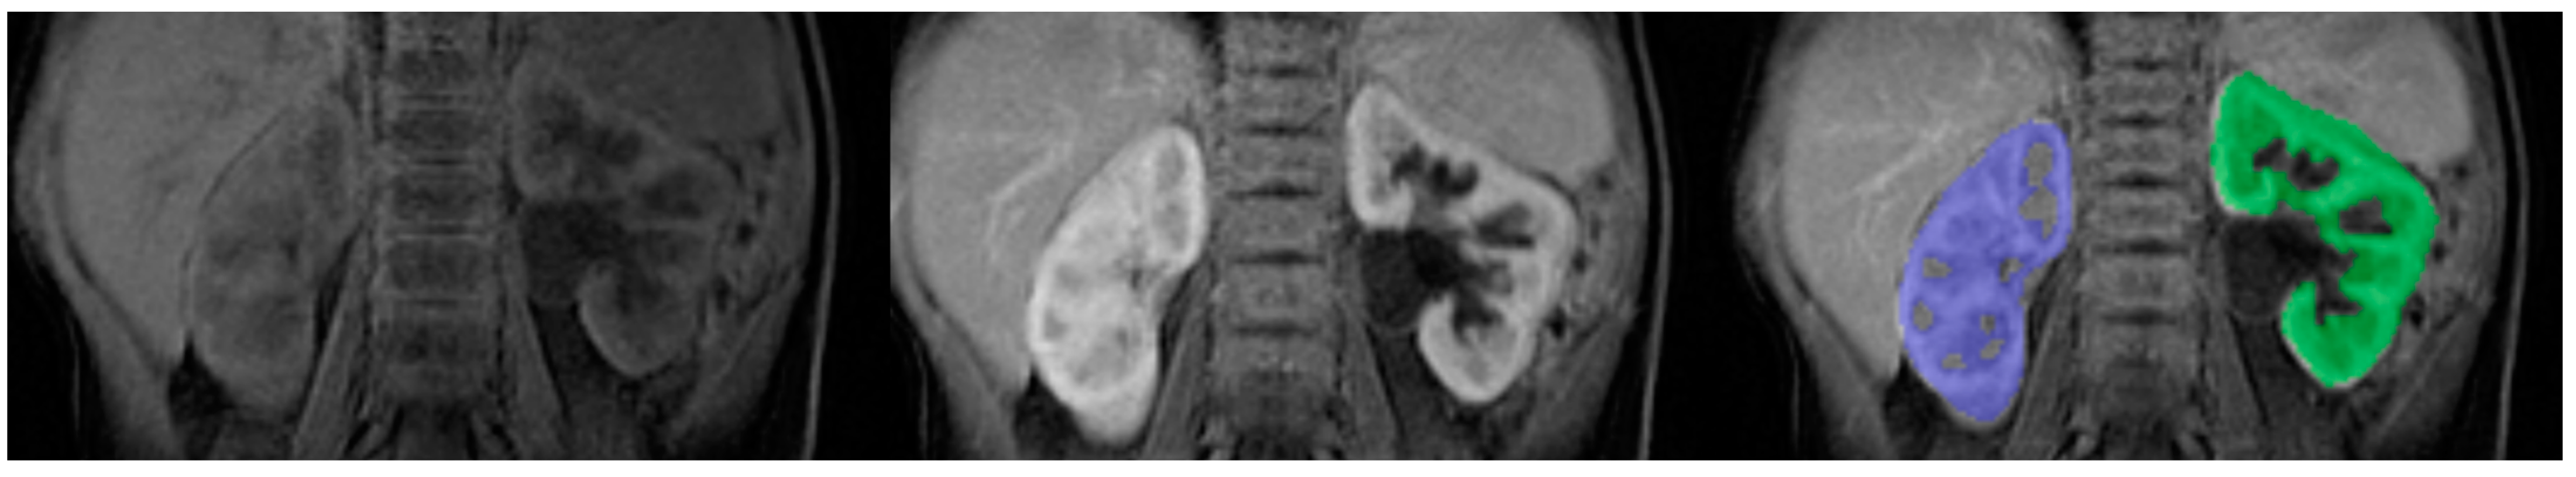

- Separation of the kidneys (Figure 4)—the number of time points was found where contrast is first seen in the calyces,